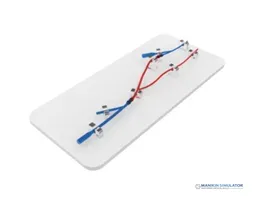

Radial Artery Puncture Operation Model (Ultrasound Guided) adalah simulator lengan bawah untuk pelatihan kanulasi arteri radialis dengan panduan USG. Arteri radialis dibuat berdasarkan data CT manusia.

Material komposit khusus memungkinkan visualisasi arteri yang jelas di layar USG *real-time*. Memberikan sensasi ‘tembus’ (*breakthrough*) yang realistis saat jarum menembus dinding arteri.

Drawing of Radial Artery Puncture Operation Model (Ultrasound-Guided)